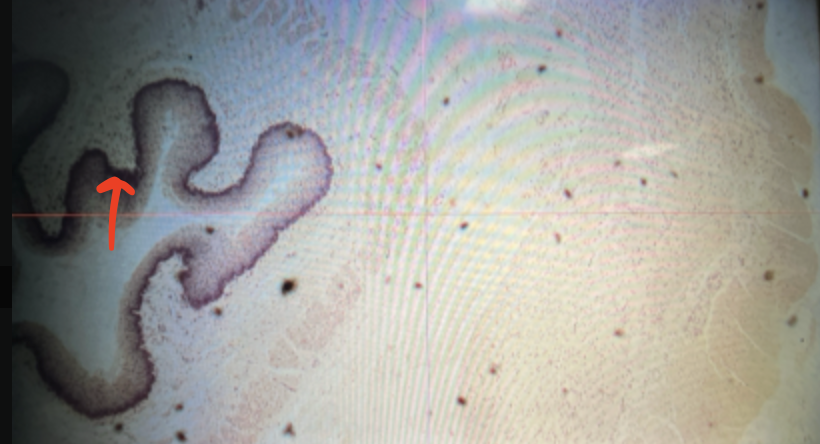

cardiac stomach

gastric pits

lumen

mucosa

mucosal epithelium

lamina propria

muscularis mucosa

submucosa

muscularis (externa)

serosa/adventitia